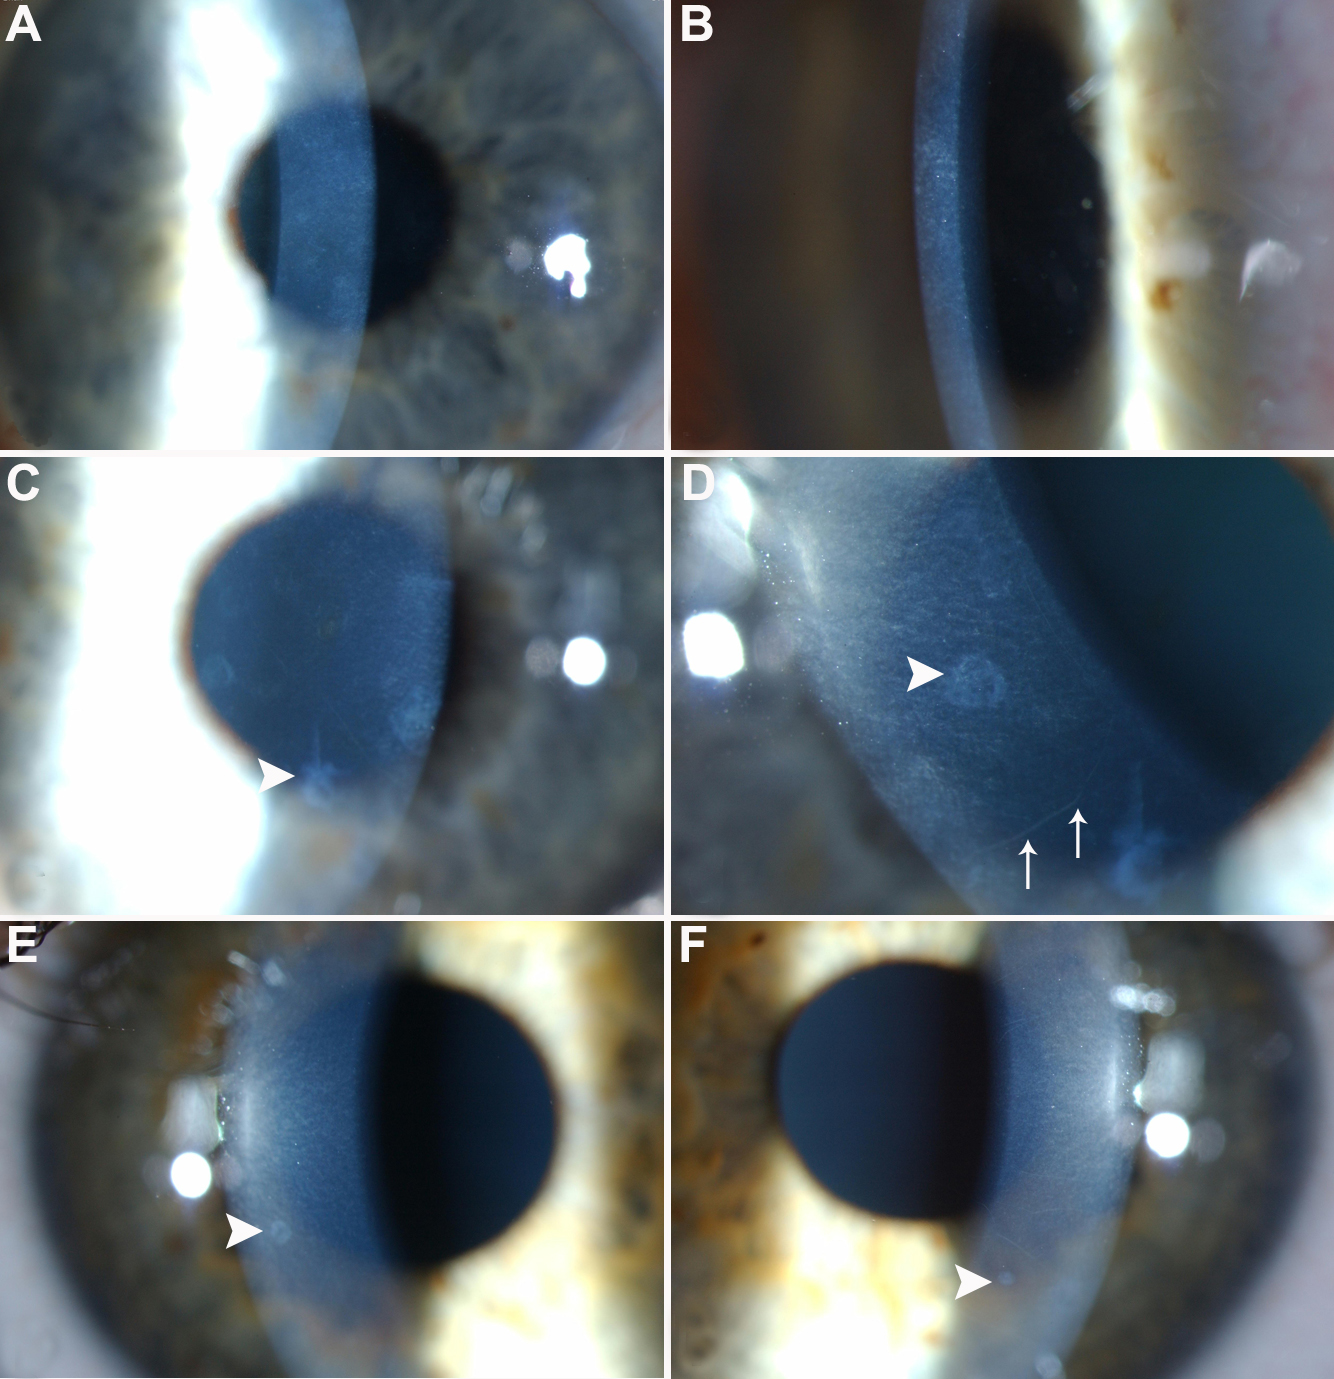

Figure 2. Slit lamp images of corneas of

affected family members. Slit lamp images of cornea highlighting

diffuse, small, gray anterior stromal flecks (A-F) and larger,

discrete circular/oval/annular gray/white opacities (0.2–1.5 mm) at the

level of Bowman's layer (C-F, small arrowheads) and prominent

corneal nerves (D, fine arrow). A: Slit lamp image of

right cornea of individual I:2, age 64 years, at 10× magnification,

demonstrating diffuse small gray anterior stromal flecks and annular

opacities. B: Slit lamp image of left cornea of individual

II:5, age 37 years, at 10× magnification demonstrating diffuse small

gray anterior stromal flecks and annular opacities. C and D:

Slit lamp images of right cornea of individual II:3, at 10×

magnification (C) and 16× magnification (D). The annular

opacities are clearly visualised (small arrowhead) with prominent

corneal nerves visible (fine arrow; E and F) Slit lamp

images of right and left corneas respectively of individual III:2, age

14 years, at 10× magnification showing the annular opacities

highlighted with arrowheads.